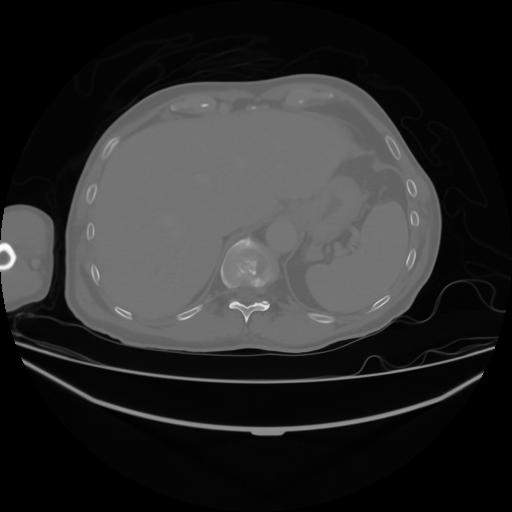

4 CUERPO,CE,Axial,3.0,CUERPO,,